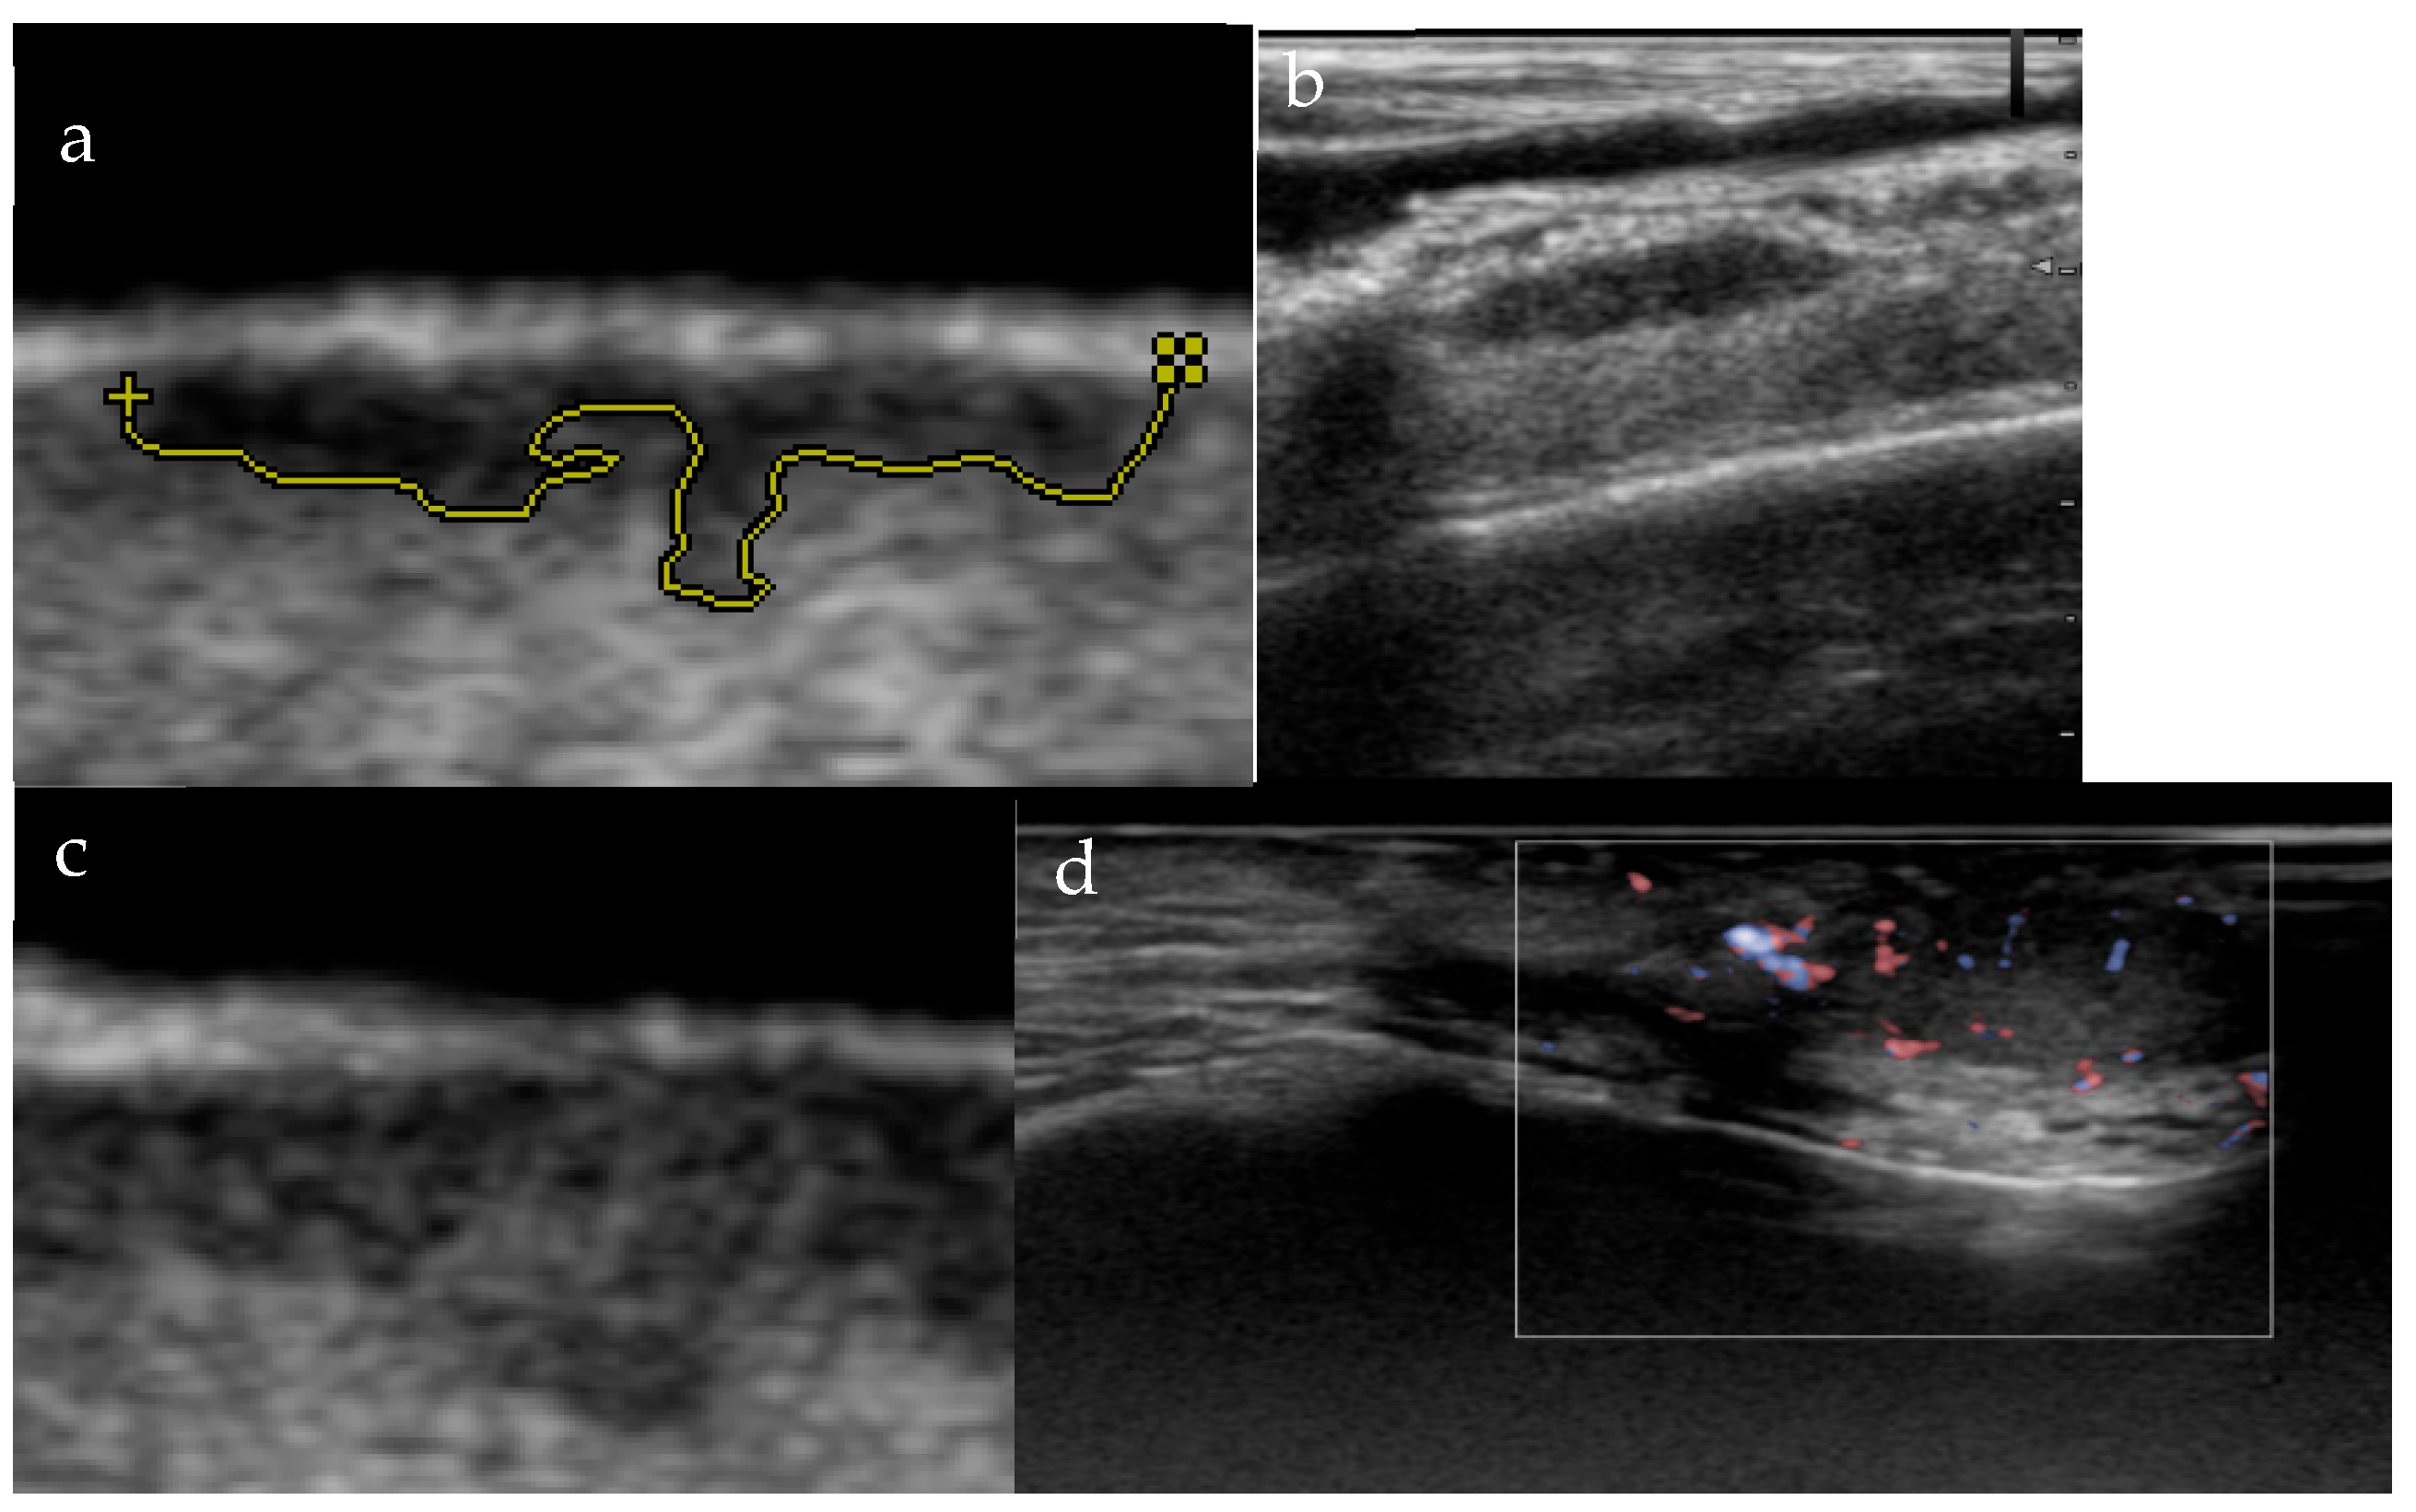

3.1. Morphology and Vascularity